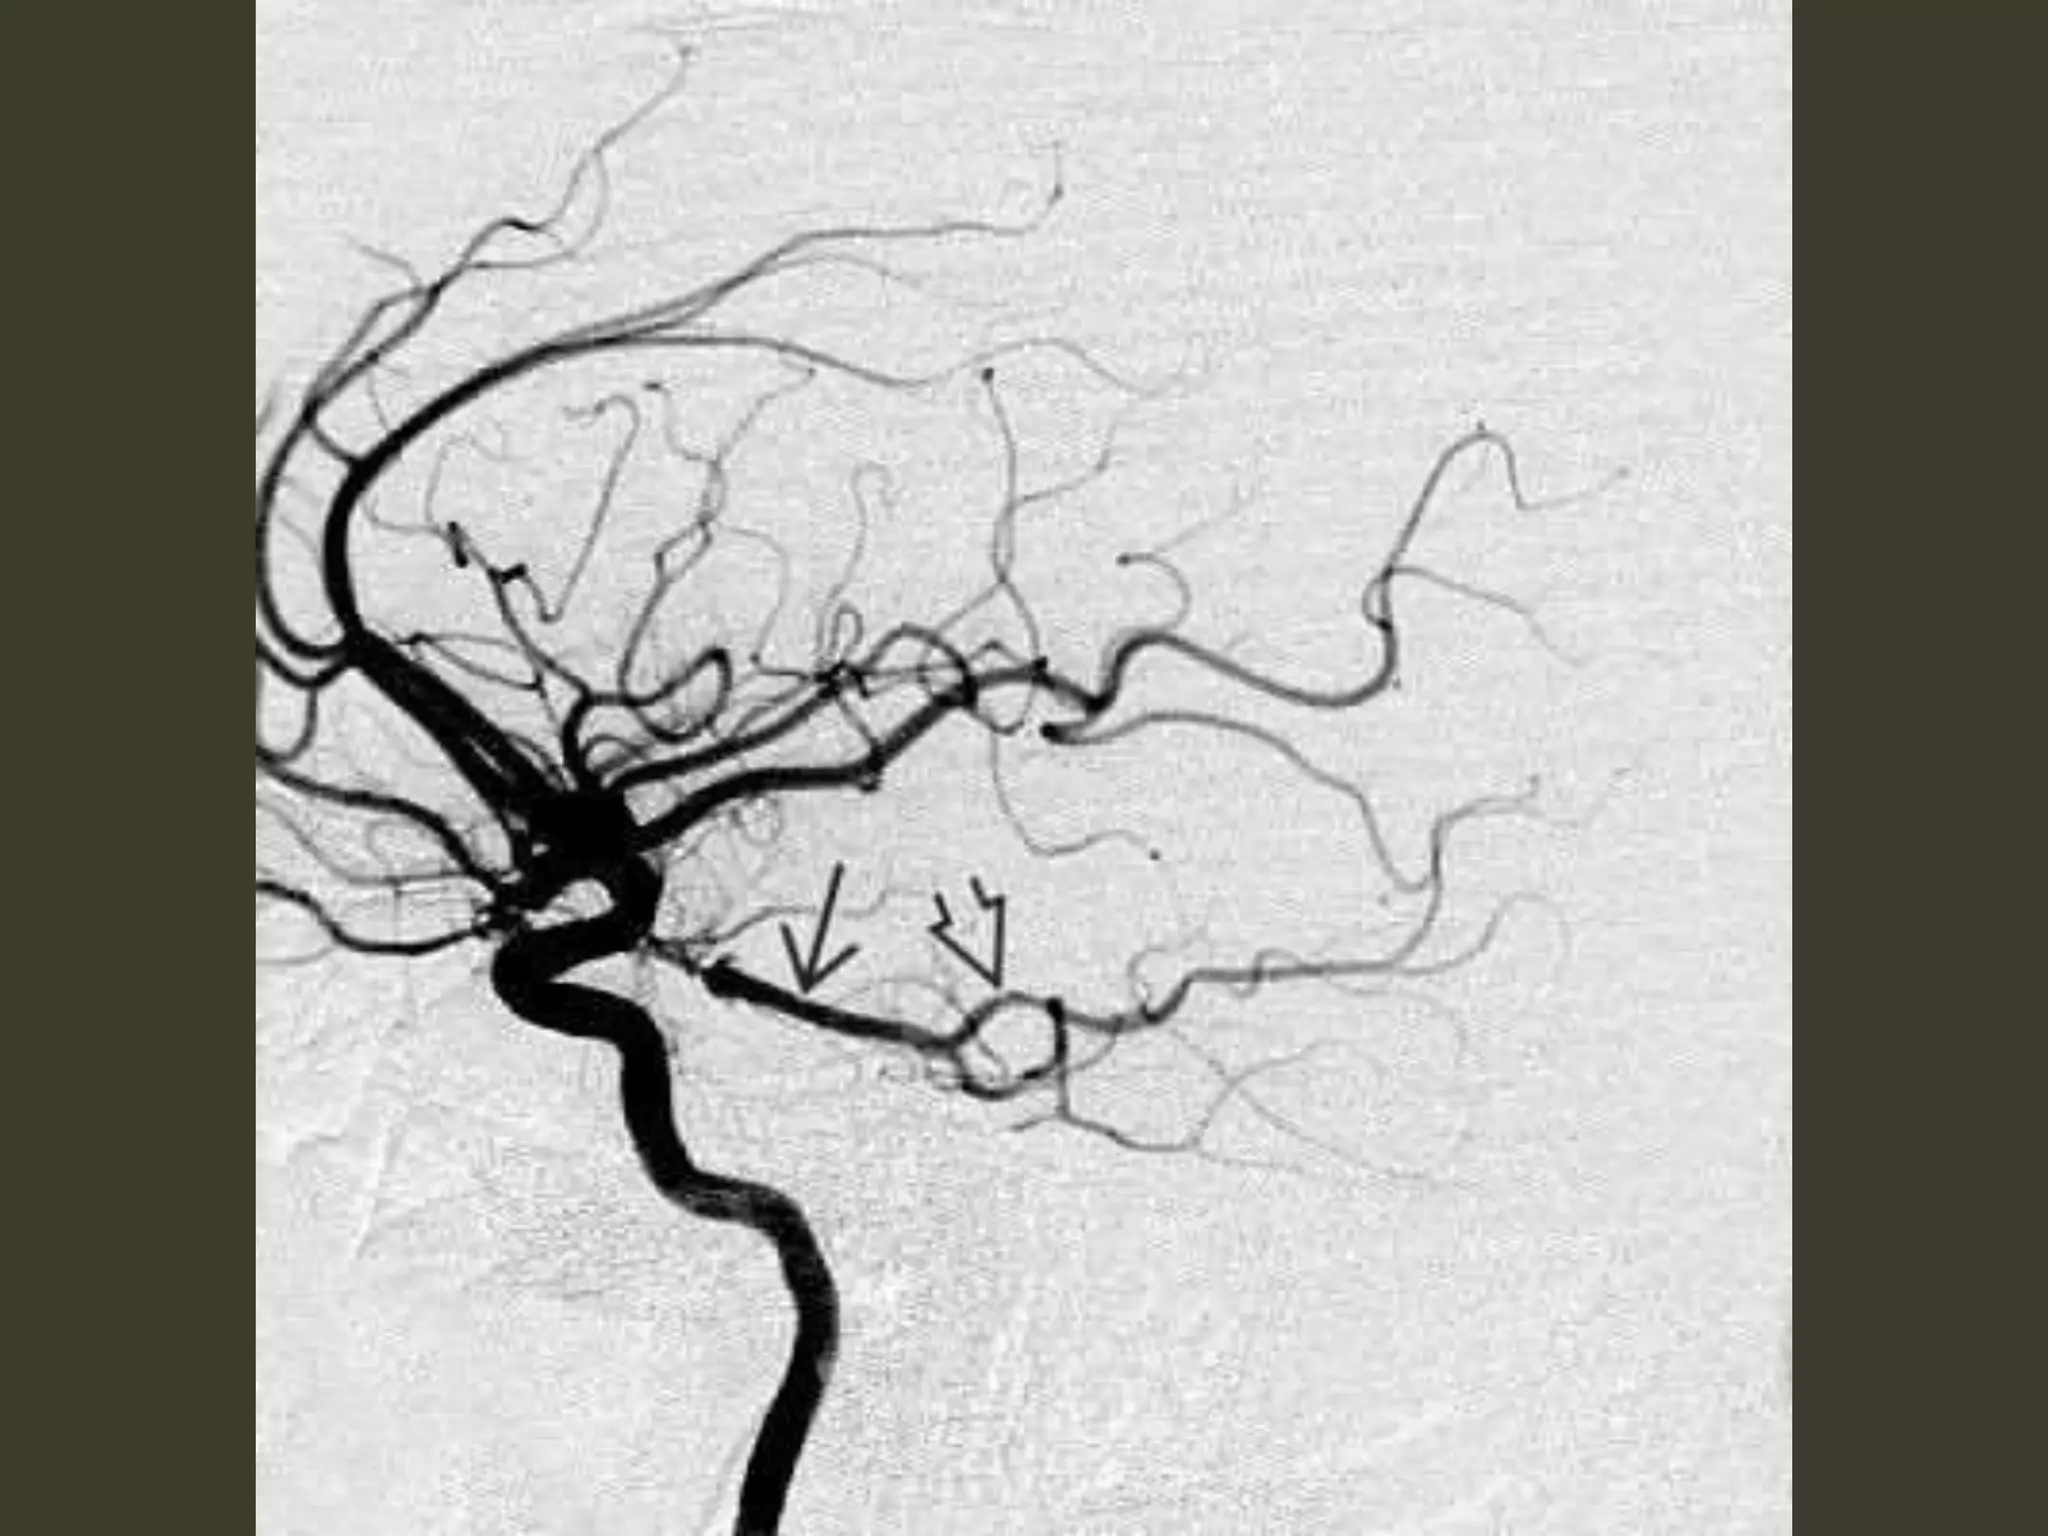

Complications • CN III(oculomotor) nerve compression – CN III palsy • PCA occlusion as it passes back up over the medial edge of the tentorium – secondary PCA (occipital) infarct

Kernohan notch • Asthe herniating temporal lobe pushes the midbrain toward the opposite side of the incisura – contralateral cerebral peduncle is forced against the hard edge of the tentorium • Pressure ischemia 🡪 ipsilateral hemiplegia – the "false localizing" sign

Duret hemorrhage "Top-down" masseffect displaces the midbrain inferiorly closes the midbrain-pontine angle Perforating arteries from basilar artery are compressed and buckled